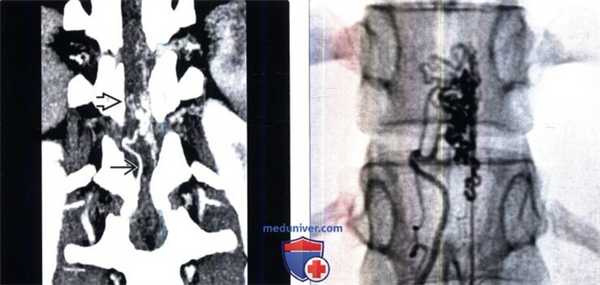

(Слева) На фронтальной КТ-ангиограмме визуализируется крупный клубок сосудов вдоль вентральной поверхности спинного мозга, кровоснабжаемый правой корешковой артерией и характеризующийся расширением вен на поверхности спинного мозга.

(Справа) Ангиография в прямой проекции: сосудистая мальформация, кровоснабжаемая корешковой артерией на поверхности спинного мозга. Шунтирование крови осуществляется на уровне спинного мозга (4 тип), а не на уровне твердой мозговой оболочки (1 тип).г) Клинические особенности: